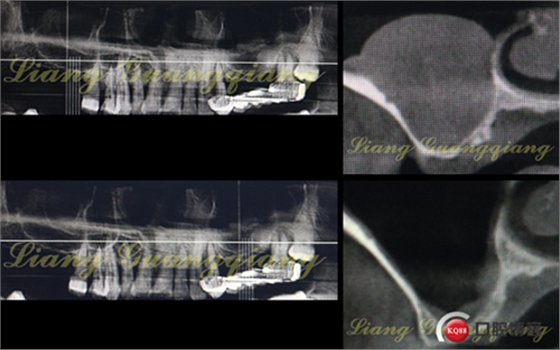

這是一周前拔牙前X光片,上頜竇內(nèi)大囊腫直徑遠(yuǎn)遠(yuǎn)>10mm。如何處理?送耳鼻喉?接下來就是預(yù)約住院,上頜竇內(nèi)手術(shù)清掃。恢復(fù)多久不知,后期是否可以繼續(xù)提升?真不好說。